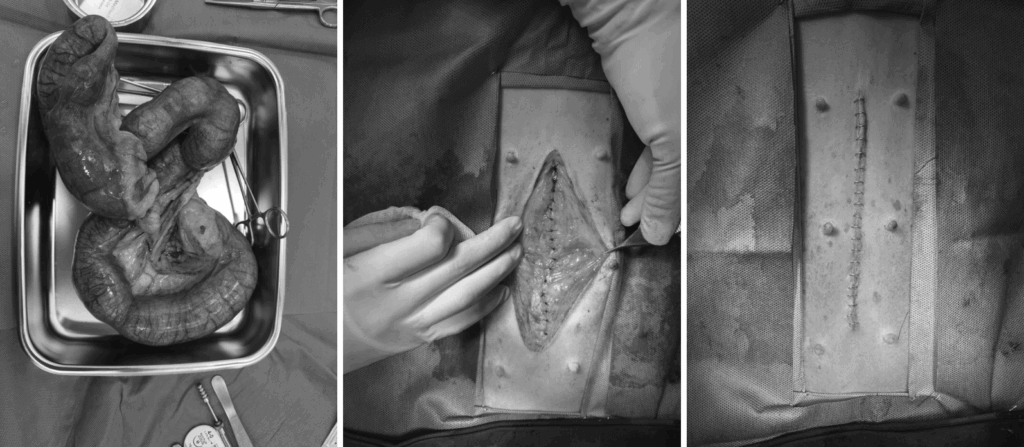

자궁축농증 수술 사진 / 온숲동물의료센터

자궁 내 분비물 / 출처: 온숲동물의료센터

자궁 적출 및 수술 사진 / 출처: 온숲 동물의료센터

수술은 저희 김영웅 대표원장님과 정형운 대표원장님이 직접 집도하셨습니다.

심하게 확장된 자궁은 안전하게 제거되었으며, 수술은 무사히 마무리되었습니다.